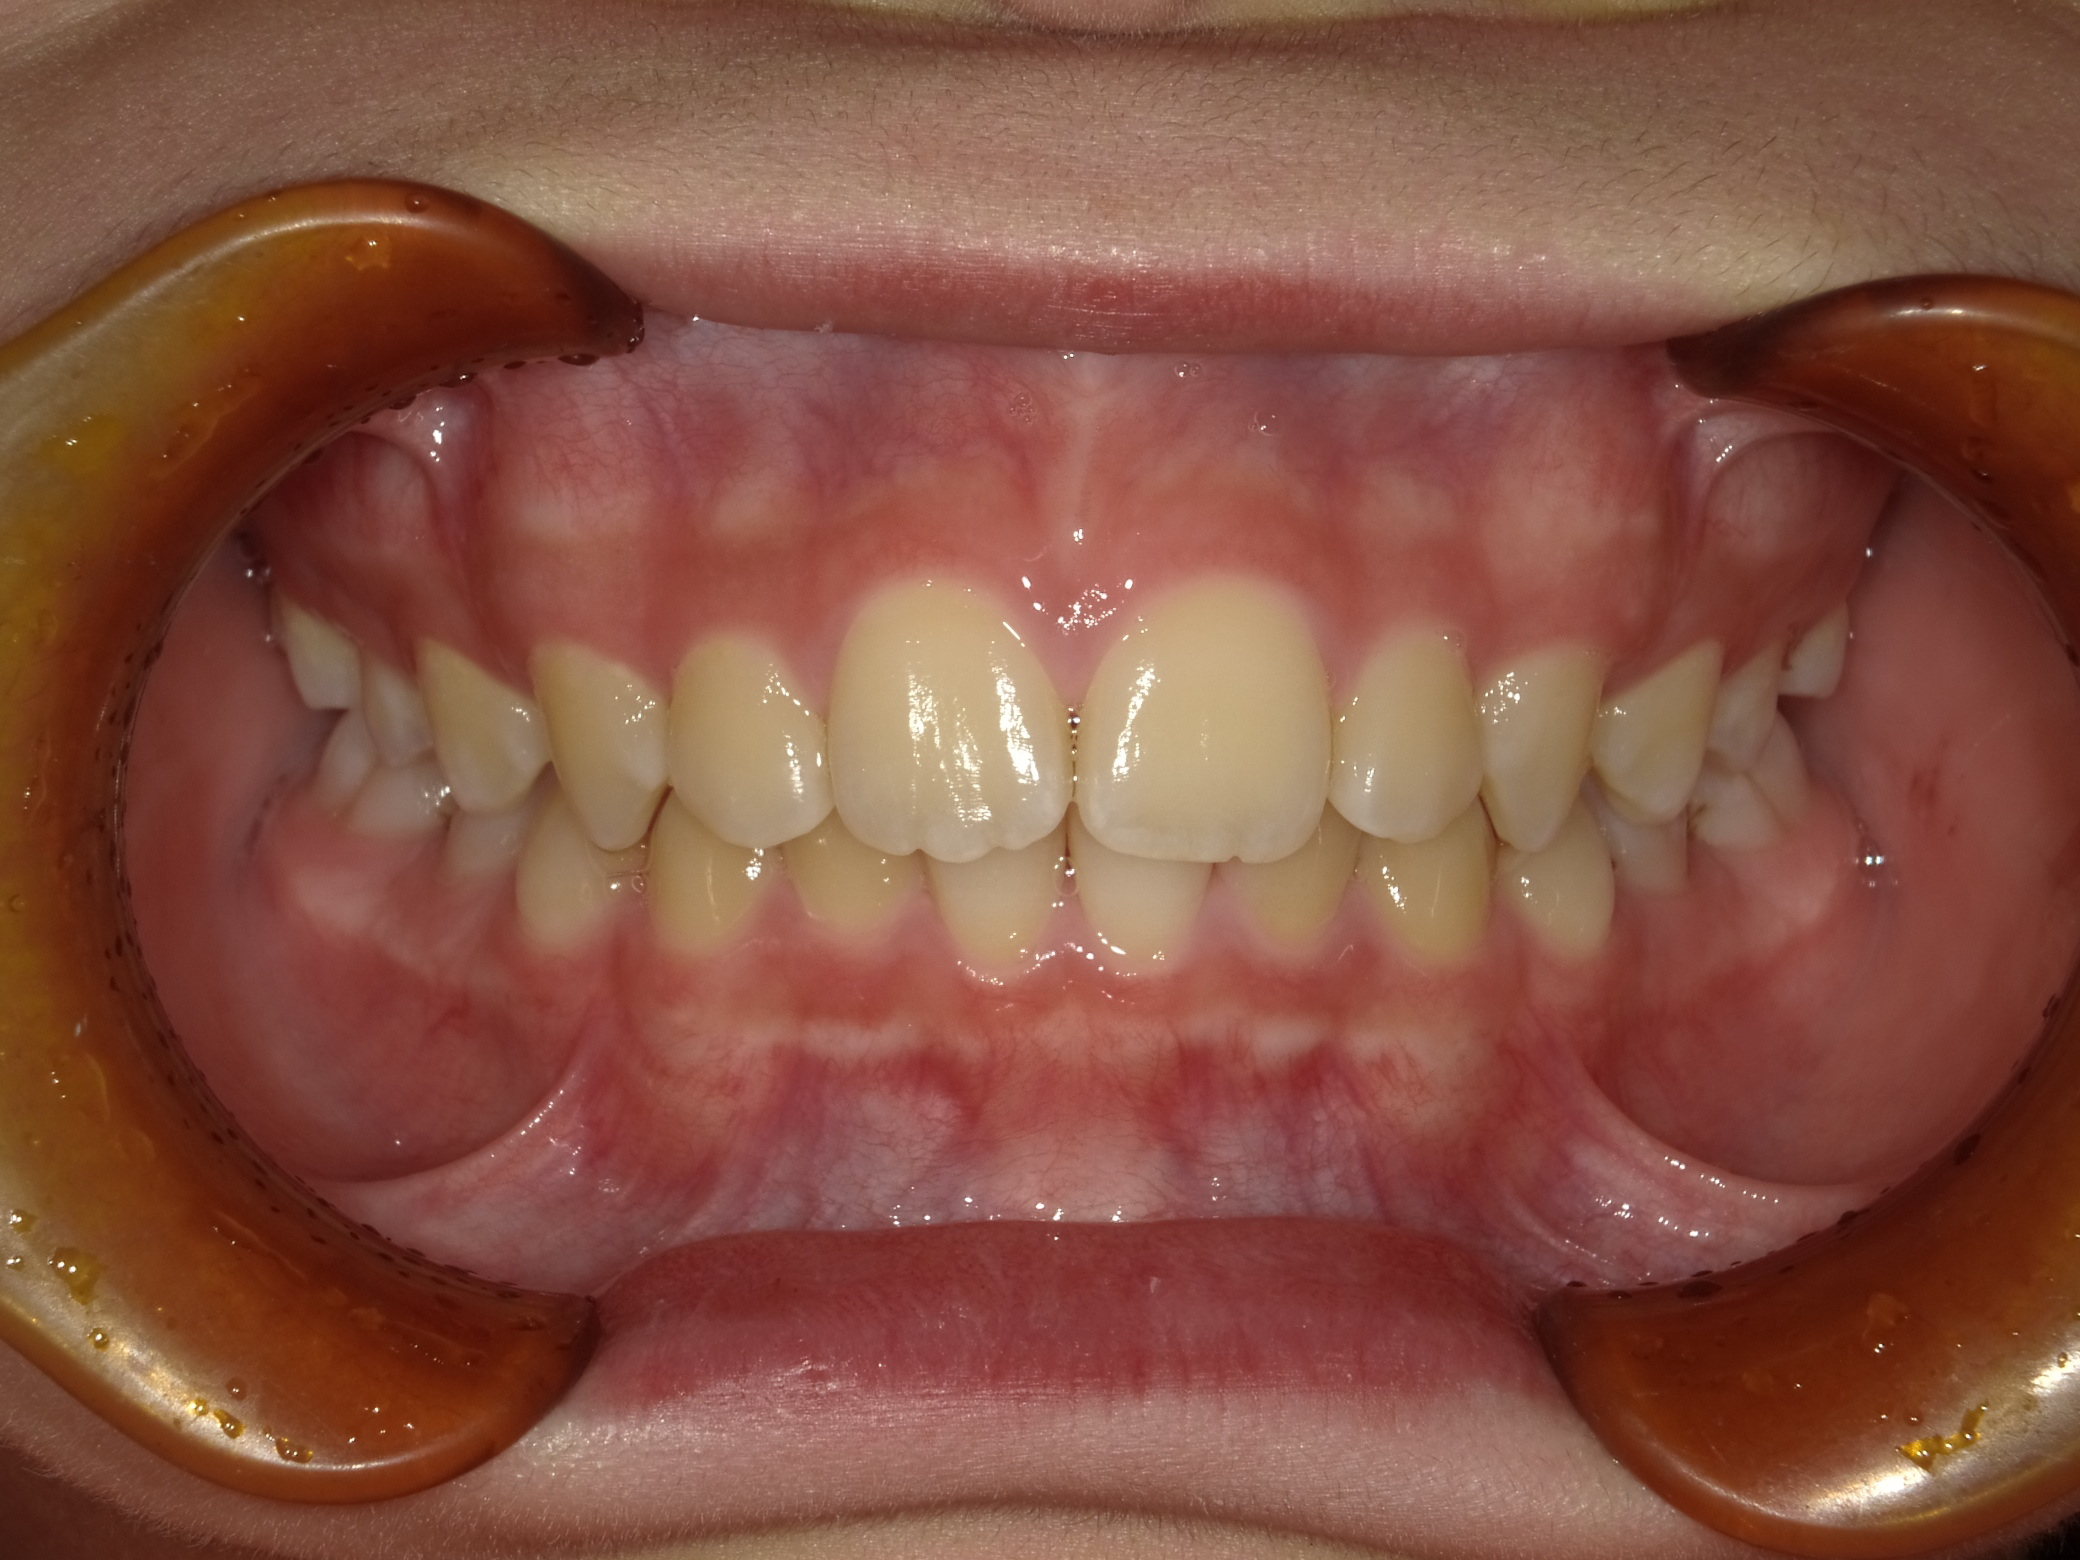

治療概要:黄色の丸の部分、まだ乳歯が抜けずに永久歯が内側から生えてきています。このままではこの乳歯は自然と抜ける可能性は低いので、まず、乳歯の抜歯を行いました。

治療前の状態

下の前歯も左右とも内側に生えている歯が並ぶスペースがなく、このままでは凸凹の状態が残ります。

また、横顔を見ても上唇が突出し、上顎前突(いわゆる出っ歯)の状態です。上の歯が下の歯を全て覆い前から見ても下の歯が見えません。

このままでは、将来的に奥歯の負担が大きくなり、歯を失う原因になる可能性があります。叢生(凸凹)の改善と、上顎前突の改善を目的に1期矯正を開始しました。